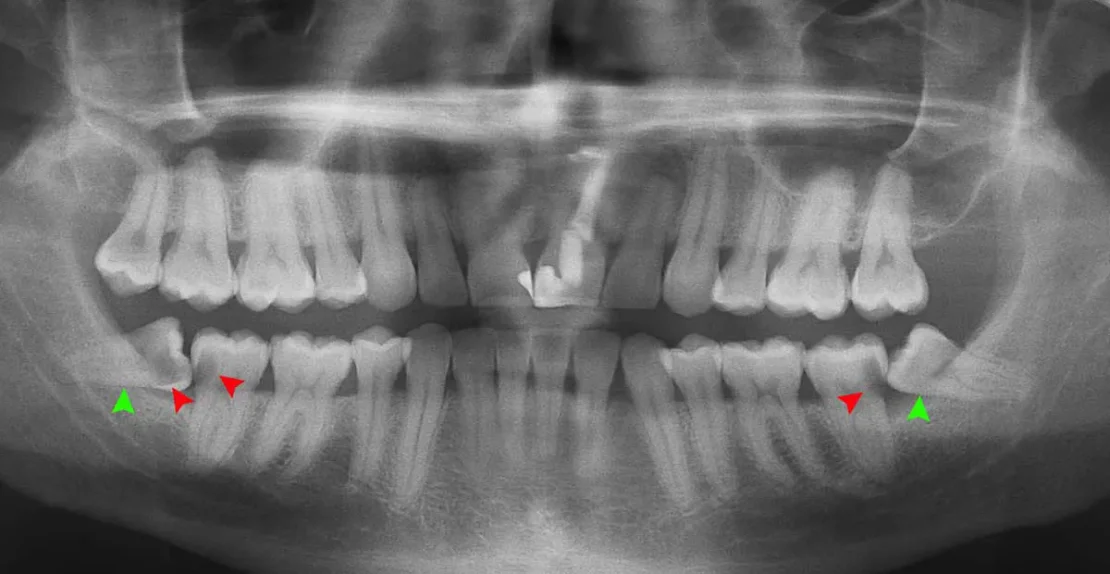

تصویر عصب کشی دندان

بررسی درمان ریشه دندان؛ راهی برای حفظ دندان آسیب دیده اما ارزشمند شما

به‌ عنوان یک دندانپزشک متخصص عصب‌کشی یا اندودنتیست، همواره با بیمارانی مواجه می‌شوم که نگرانی‌های زیادی درباره درمان ریشه یا همان عصب‌ک...